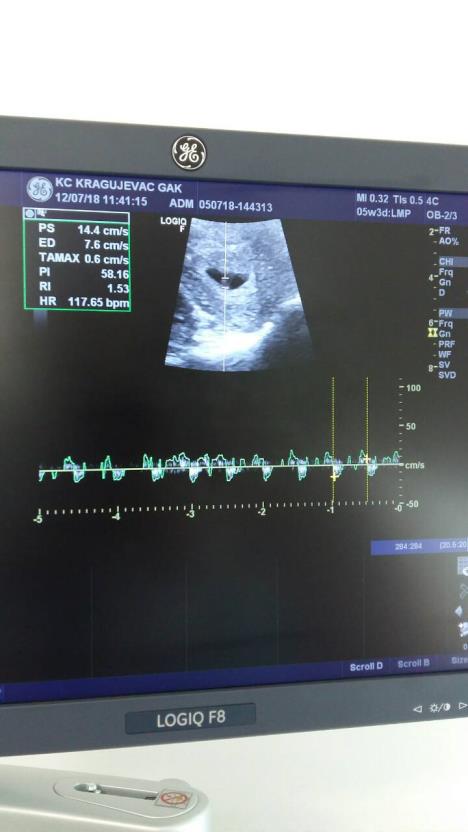

U centru za vantelesnu oplodnju u Kliničkom centru Kragujevac, danas su uspešno vraćena dva embriona.

Od kada je u martu mesecu osnovan Centar za BMPO u Kliničkom centru Kragujevac, na području centralne Srbije koja obuhvata oko dva miliona stanovnika, od Novog Pazara do Aranđelovca, 321 par prošao Drugostepenu komisiju i upućen na dalje lečenje u Srbiji. Danas u vreme naše posete uspešno su urađene dve vantelesne oplodnje i potvrđeno da se u oba slučaja oformio plod.